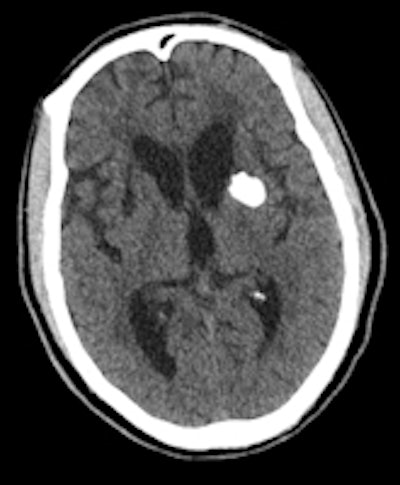

A 60-year-old man known to have HIV presented with seizures. The solid calcifications on noncontrast enhanced CT (NCECT) at the right frontal (left), left basal ganglia (middle), and right parietal areas (right) represent sequela following treatment for documented toxoplasmosis. All images courtesy of Dr. Froilan Celzo.

The dense calcifications seen in patients with congenital toxoplasmosis can also have a random distribution, with lesion sizes that correlate with the duration of infection. Treatment can result in shrinkage and even resolution of these calcifications (see figure).